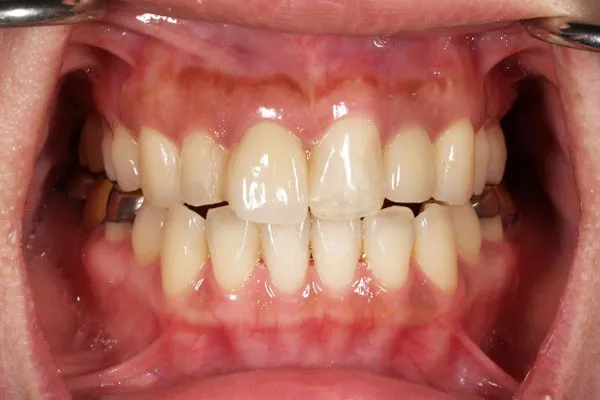

39歳 / 女性

上の前歯2番目と3番目の左右が乳歯のままで大人の歯が生えてこない。これから どうしたら良いのか相談したい。

治療内容

ガイディッドサージェリーにてインプラントを埋入。上の前歯に4本埋入。

治療期間

インプラントが骨につくまで4か月。治療終了までに約1年。

• Before前

• After後